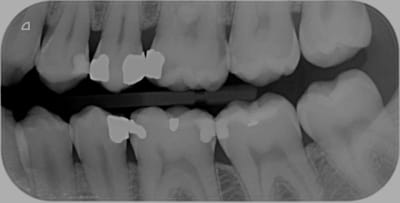

Hors la has recommande la cotation de clichés rétro coronaires au niveau molaire et prémolaire je cite " en l'absence d'une situation clinique spécifique" donc en prévention je suppose. quelle est leur cotation ? 1 à 3 dents contiguës comme les rétro alvéolaires ? ou que dalle ? Au niveau incisif pas de radio nécessaire les caries pouvant etre détectables aisément selon le guide de bonnes pratiques.

Personnellement, à chaque bilan annuel, c'est détartrage et 2 BW (un à droite, et un à gauche), donc Z12, et avec ça, j'ai une bonne vue d'ensemble. Pas la peine de faire toutes les radios que tu fais!

LIBELLE : Radiographie intrabuccale rétroalvéolaire et/ou rétrocoronaire d'un secteur de 1 à 3 dents contigües

Ca ne change rien. Ces radios doivent TOUTES être justifiées quelque soit le nom qu'elles portent. Ce qui va être justifié par contre c'est le traitement des caries qui seront passées au travers d'un simple examen visuel endo buccal et qui vont se manifester tot ou tard par un signe d'appel. La, c'est bon feu vert pour un Z6 et le R25 à suivre.

C'est pour ça qu'un contrôle à la panoramique est largement suffisant en France . Suffisant pour voir les péches et les grosses caries. En plus en baissant la pano à z16 ça fait presque plus mal au cœur de ne pas la facturer. Cachez moi ces caries interproximales débutantes que je ne saurai voir !!

Excuses moi mais débutantes c'est une rétro alvéolaire (ou rétro coronaire) qu'il faut faire. C'est ce qu'on fait quand on a un pano en cas de doute , non ?

Quand je pense aux nombres de caries interproximales ou lésions apicales qu'on découvre fortuitement sur des rétros.....!

Je fais des rétros à chaque contrôle avec souvent un détartrage, et que cela soit ça ou pano, je vois mal comment on peut nous dire que cela n'est pas justifié?

Le patient vient faire sa visite annuelle, sans rétros je suis incapable de lui assurer que tout va bien....!

HBQK142 Radiographies intrabuccales rétroalvéolaires et/ou rétrocoronaires de 8 secteurs distincts de 1 à 3 dents contigües Z6+7Z6 63.84 rx